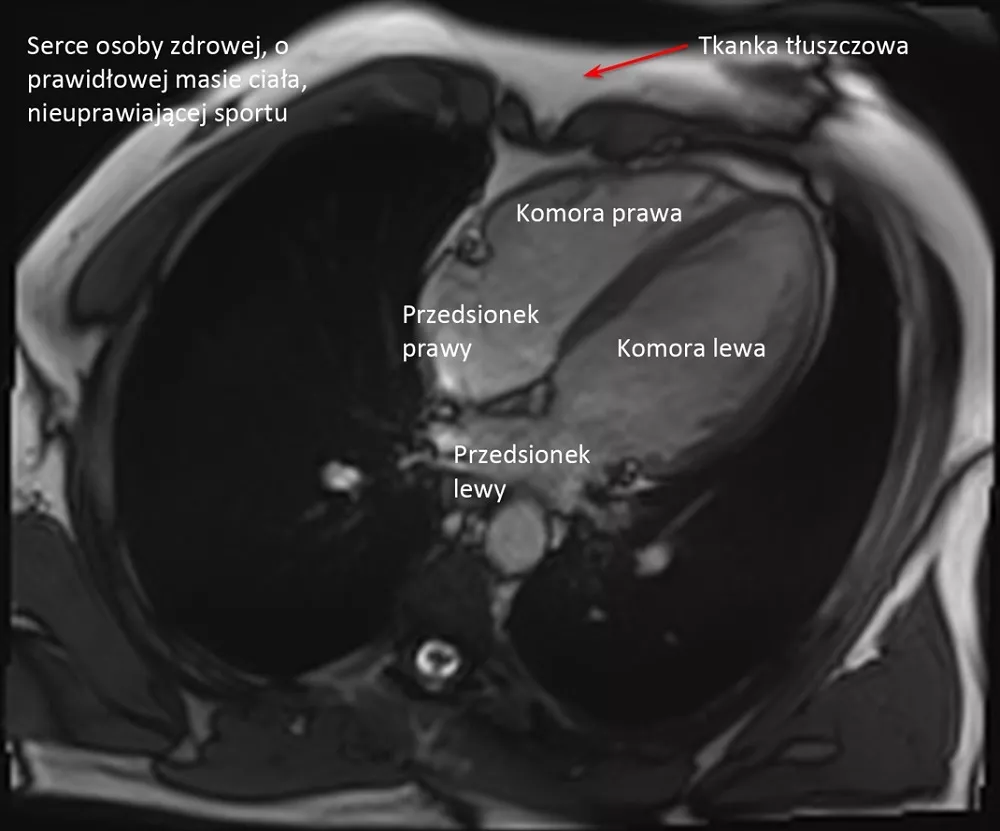

– Organizm osoby biegającej długo i duże objętości, trenującej wiele godzin tygodniowo, podlega tak zwanym zmianom adaptacyjnym. Jestem kardiologiem, więc powiem jak to wygląda patrząc od strony serca: zwalnia się rytm, serce jest bardziej spokojne, powiększają się jamy serca.

Tak, bo serce takiego biegacza bije 40 razy na minutę i jest powiększone. I taki lekarz mówi, że to bardzo niedobrze i żeby jak najszybciej zaprzestać biegania, a przynajmniej mocno zmniejszyć jego intensywność. Tymczasem... w większości wypadków są to właśnie normalne zmiany adaptacyjne, a organizm w ten sposób przystosowuje się do dużej intensywności, szczególnie jeśli trwa to latami.

Obu komór i obu przedsionków. One wszystkie powiększają się symetrycznie. Grubieje także trochę mięsień, natomiast raczej nie poszerza się aorta. Kurczliwość mięśnia sercowego w spoczynku może być na granicy dolnej normy, bo ono wtedy odpoczywa, natomiast w wysiłku radzi sobie i reaguje znakomicie.

W porównaniu do grupy kontrolnej, czyli mężczyzn w tym samym wieku nie uprawiających sportu, nie stwierdziliśmy żadnych cech uszkodzenia mięśnia sercowego czy anomalii w funkcjonowaniu układu krążenia, za to większość parametrów była znacznie korzystniejsza: cholesterol był niższy, tkanka tłuszczowa mniejsza, lepsze ciśnienie krwi. To wszystko pokazuje, że ultra jest korzystne dla zdrowia serca.